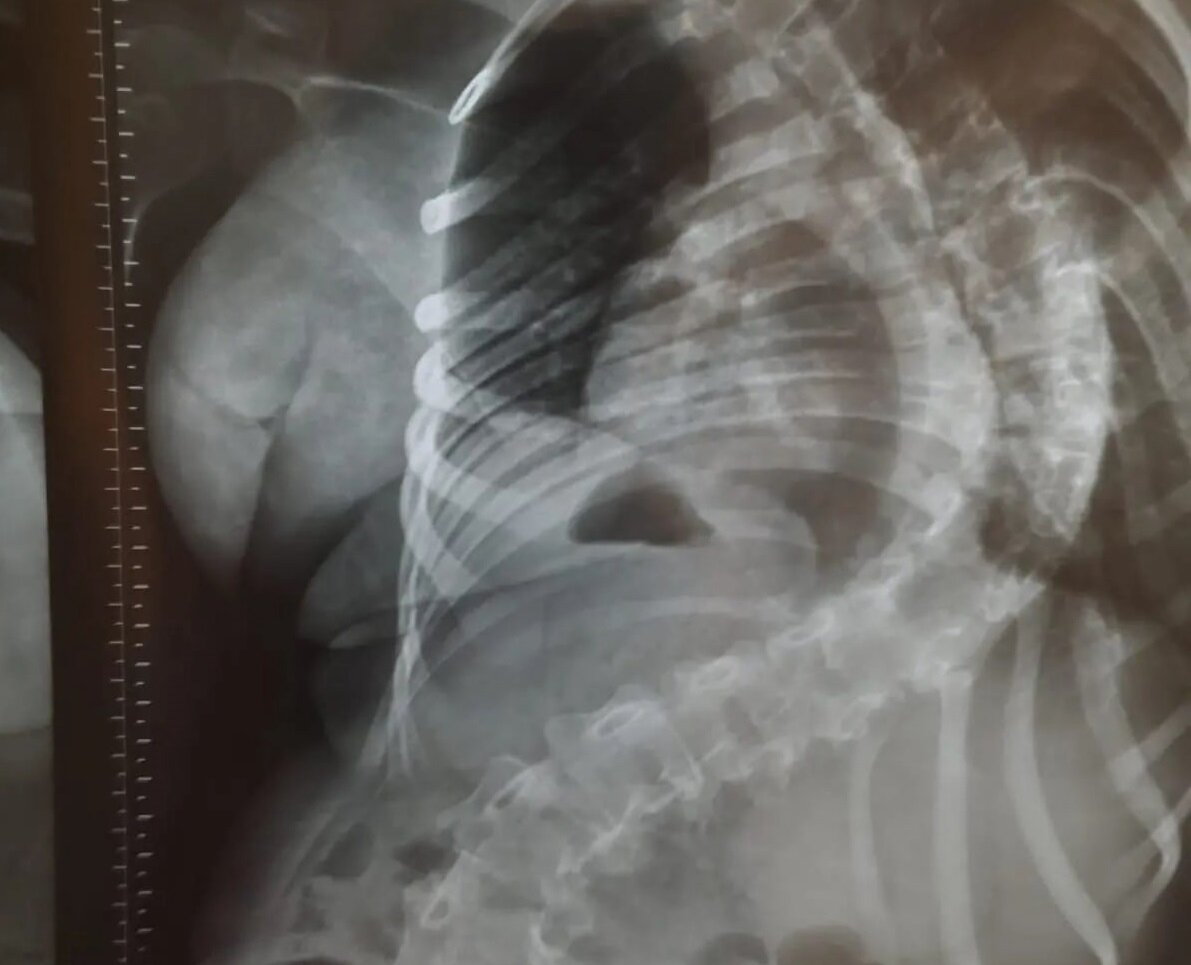

Но нет. Вскоре у Светы появился ужасный сколиоз. Позвоночник стал искривляться. И остановить этот процесс не удаётся. Света уже не может нормально дышать. На внутренние органы идёт постоянное давление. А ещё это очень больно. Не спасают ни корсет, ни обезболивающие.

Самое ужасное в этом то, что Свете не могут больше делать инъекции Спинразы, которые нужны регулярно. Препарат вводят прямо в позвоночник, из-за сколиоза это стало невозможным.

Сейчас Свете нужна операция на позвоночнике. Стоимость лечения — 4 123 655 рублей. Мы просим совсем немного вашей любви. Помогите собрать нужную сумму. Сделайте пожертвование прямо сейчас. Спасите Свету! Мы верим в ваши добрые сердца!